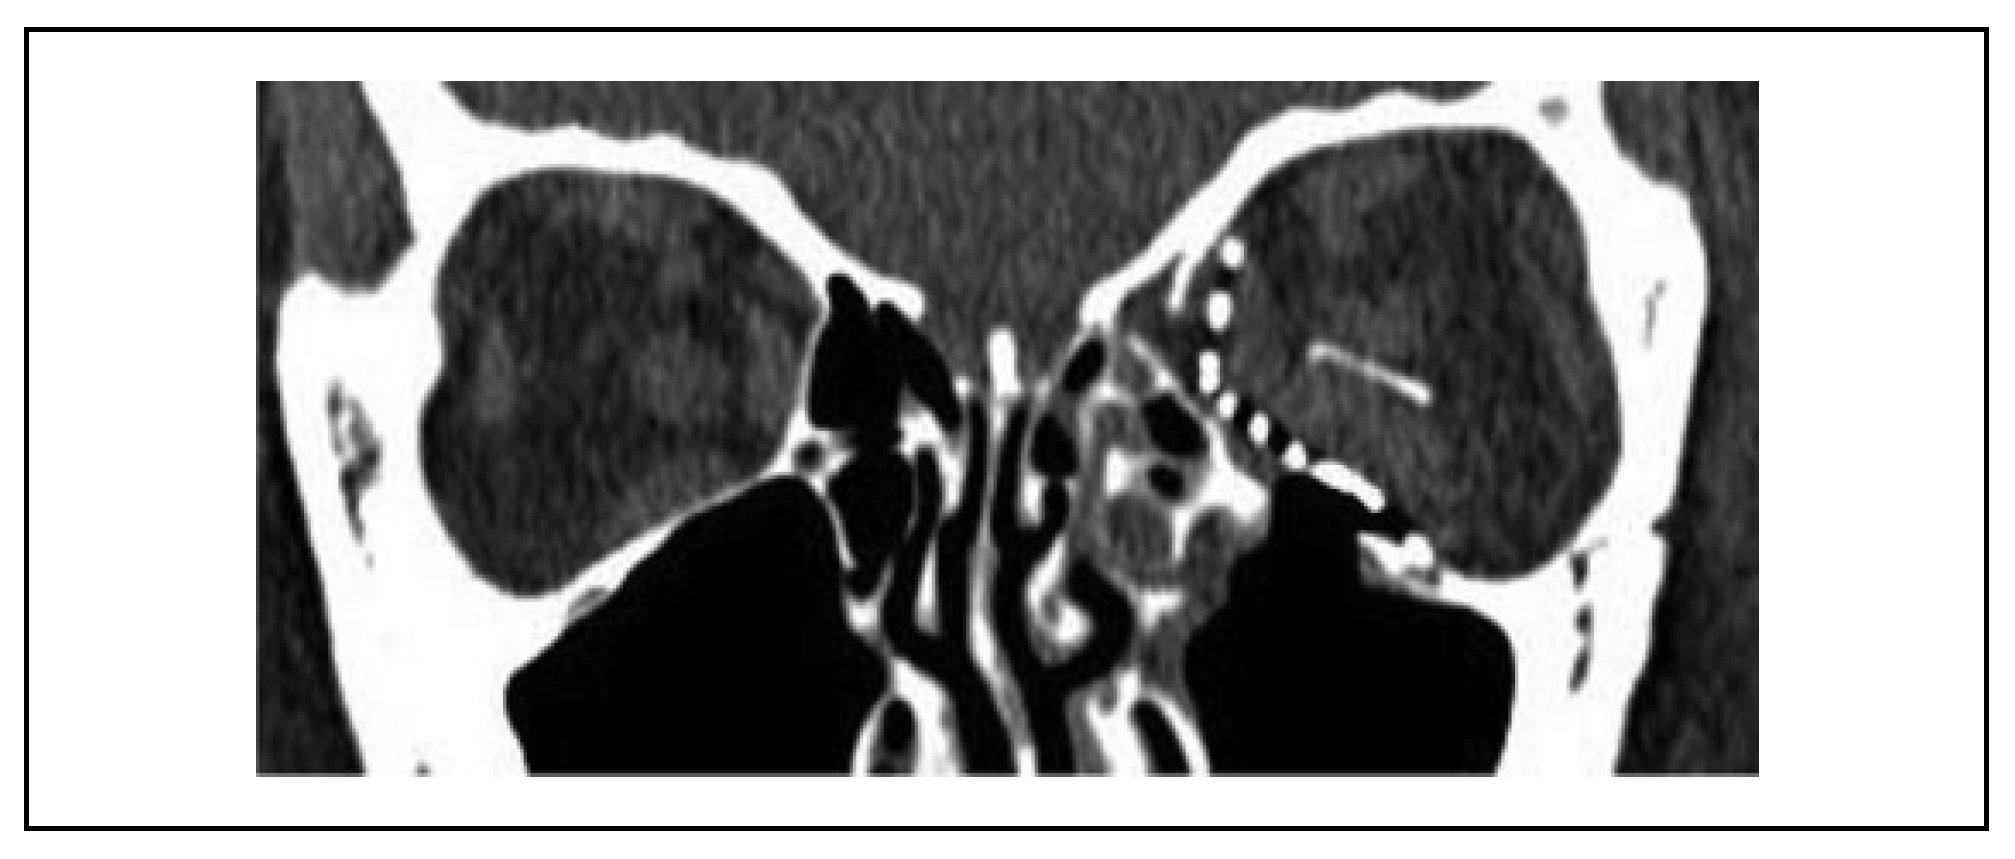

Case Report